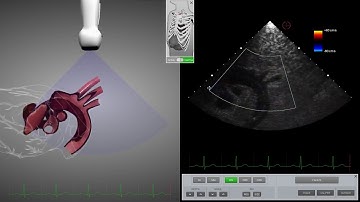

echocardiogram tee:localized dissection 1/3of the ascending aorta